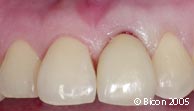

47. | 戴入一体化基台冠1周后。 |

48. | 病人的微笑。 |